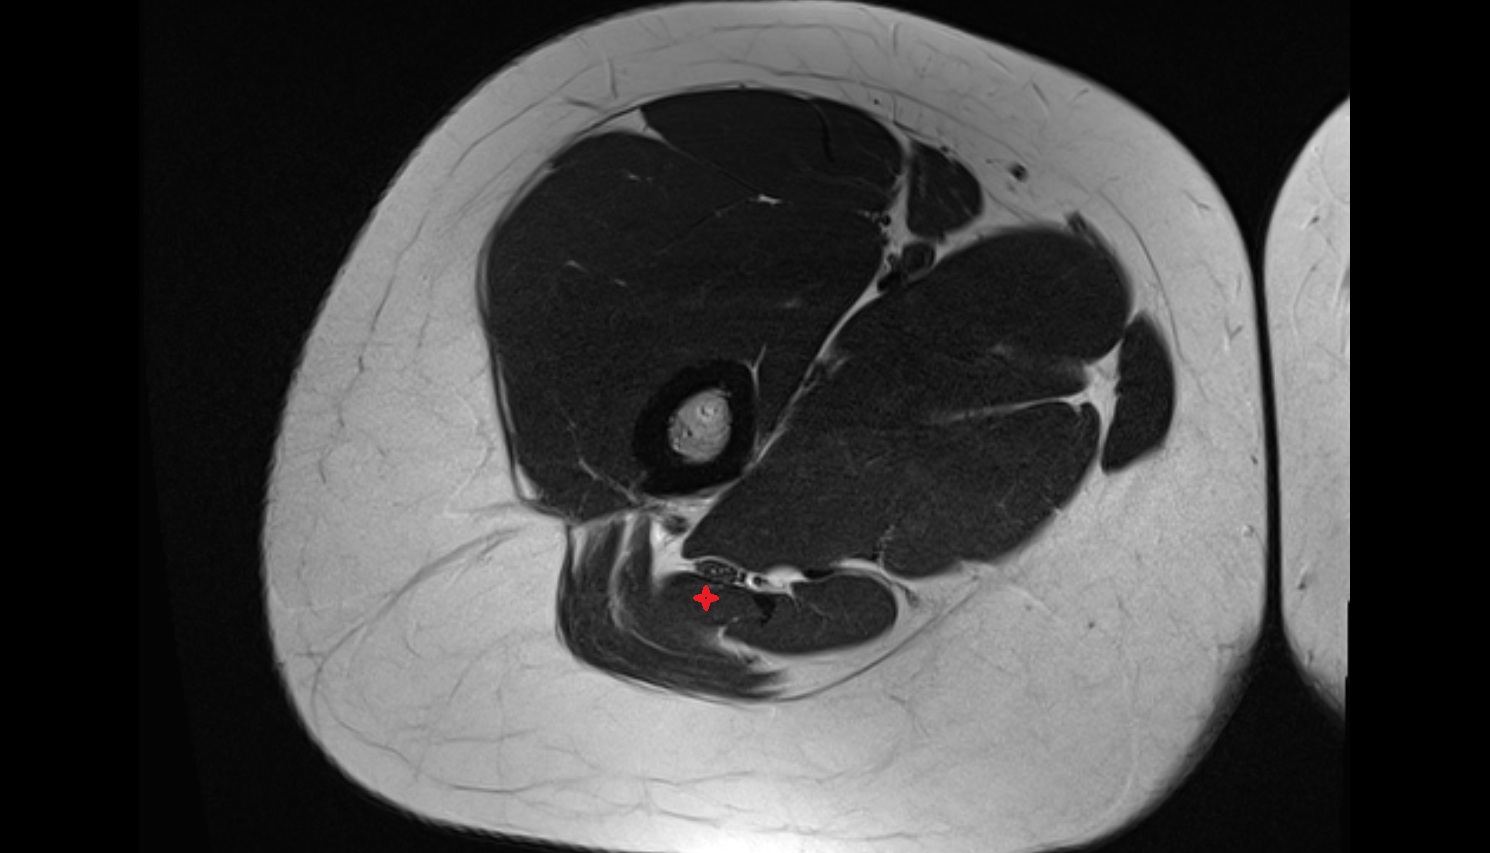

- Iliopsoas muscle

- Vastus intermedius muscle

- Quadratus femoris muscle

- Rectus femoris muscle

- Sartorius muscle

- Tensor fasciae latae muscle

- Vastus lateralis muscle

- Vastus medialis muscle

- Biceps femoris muscle (Short head)

- Biceps femoris muscle (Long head)

- Semitendinosus muscle

- Semimembranosus muscle